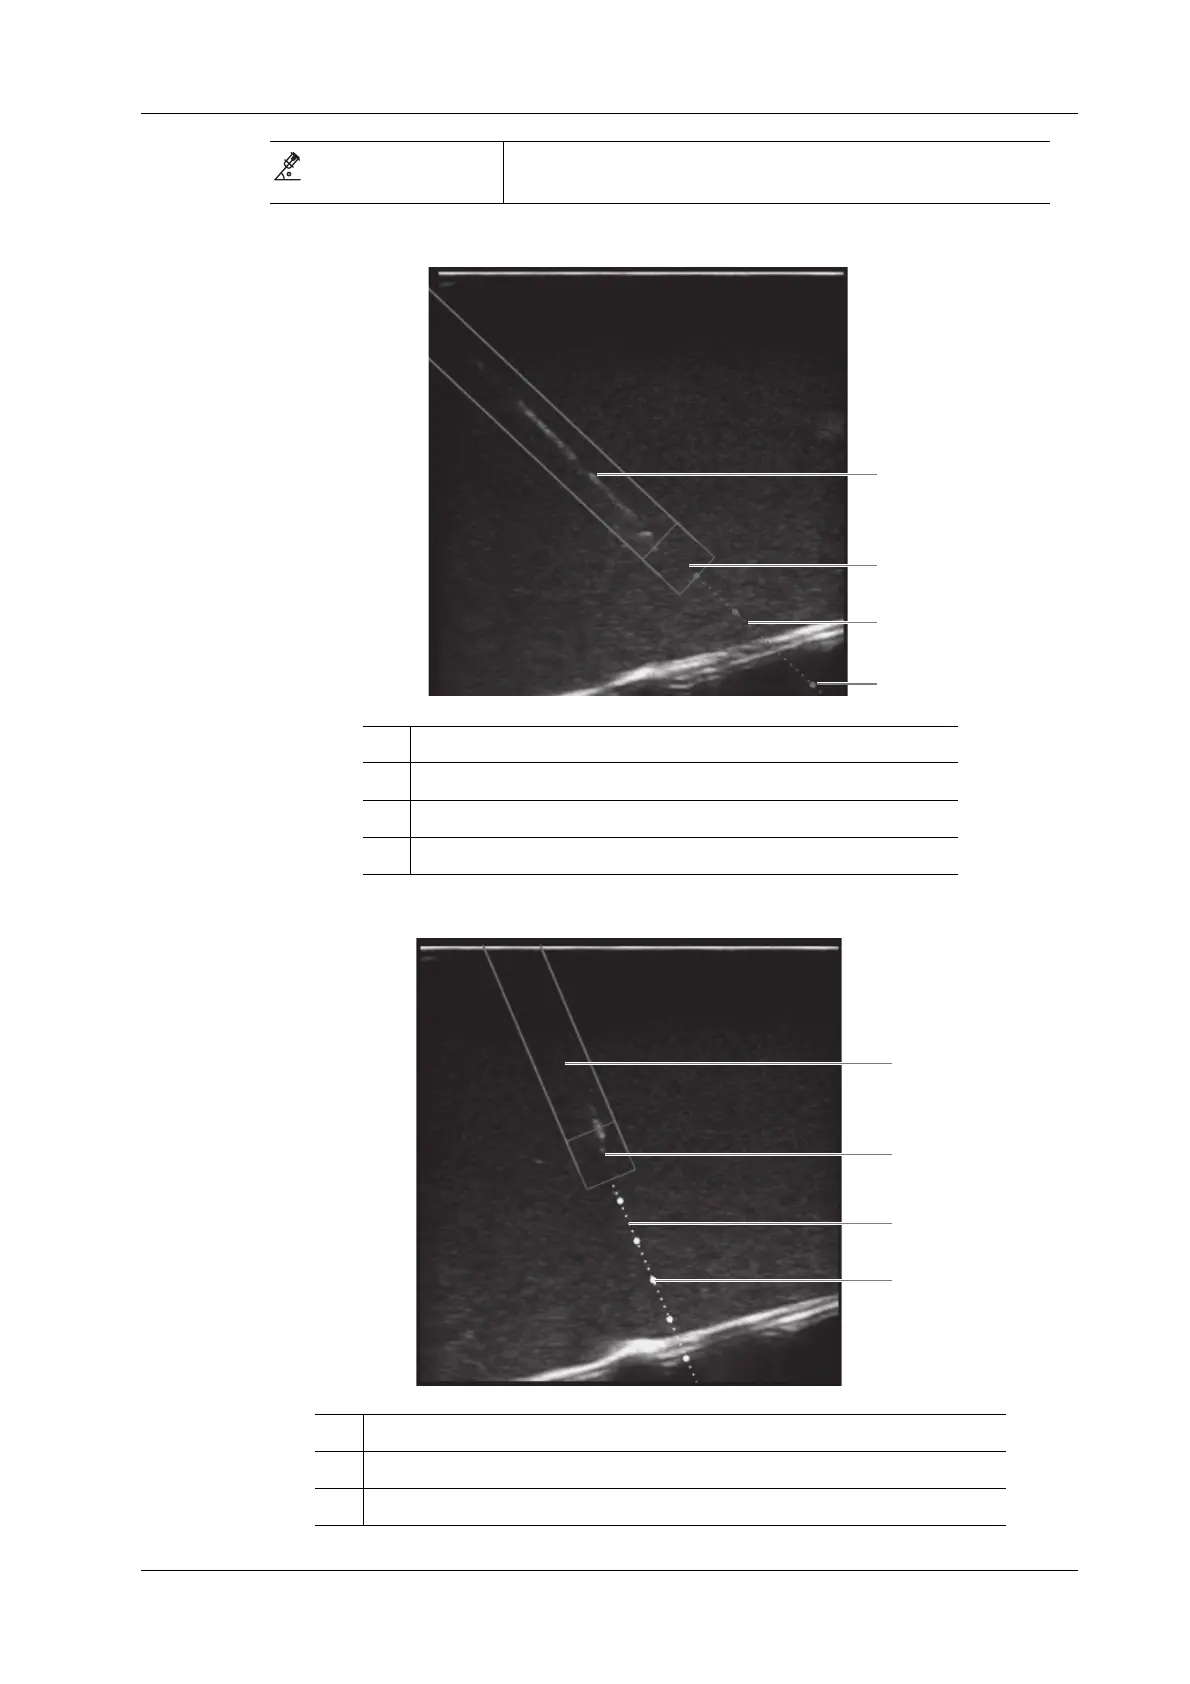

In Plane Needle Guidance GUI

Out of Plane Needle Guidance GUI

Appears when the insertion angle of a needle relative to the skin

surface exceeds 60° to notify users to adjust the angle.

1 Needle position in the ultrasound plane

2 Needle tip position in the ultrasound plane

3 Needle guidance trajectory

4 Scale of guideline (5 mm/scale)

1 Needle projection position in the ultrasound plane

2 Position at which the needle cross the ultrasound plane

3 Projection position of the needle guidance trajectory in the ultrasound plane